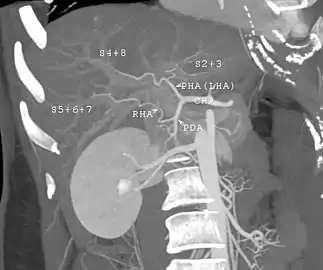

With the recent advances of noninvasive imaging, living liver donors usually have to undergo imaging examinations for liver anatomy to decide if the anatomy is feasible for donation. The evaluation is usually performed by multidetector row computed tomography (MDCT) and magnetic resonance imaging (MRI). MDCT is good in vascular anatomy and volumetry. MRI is used for biliary tree anatomy. Donors with very unusual vascular anatomy, which makes them unsuitable for donation, could be screened out to avoid unnecessary operations.

MDCT image. Arterial anatomy contraindicated for liver donation

MDCT image. Portal venous anatomy contraindicated for liver donation

MDCT image. 3D image created by MDCT can clearly visualize the liver, measure the liver volume, and plan the dissection plane to facilitate the liver transplantation procedure.